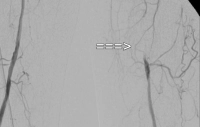

Filmbeispiel: TASC C → offene Rekonstruktion

AVK Stadium IIb links (Gehstrecke unter 100 m). Die präoperative DSA zeigt:

- eine subtotale Stenose der Arteria femoralis communis

- einen langstreckigen Verschluss der Arteria femoralis superficialis im Adduktorenkanal

- Teilverschlüsse der Unterschenkelarterien